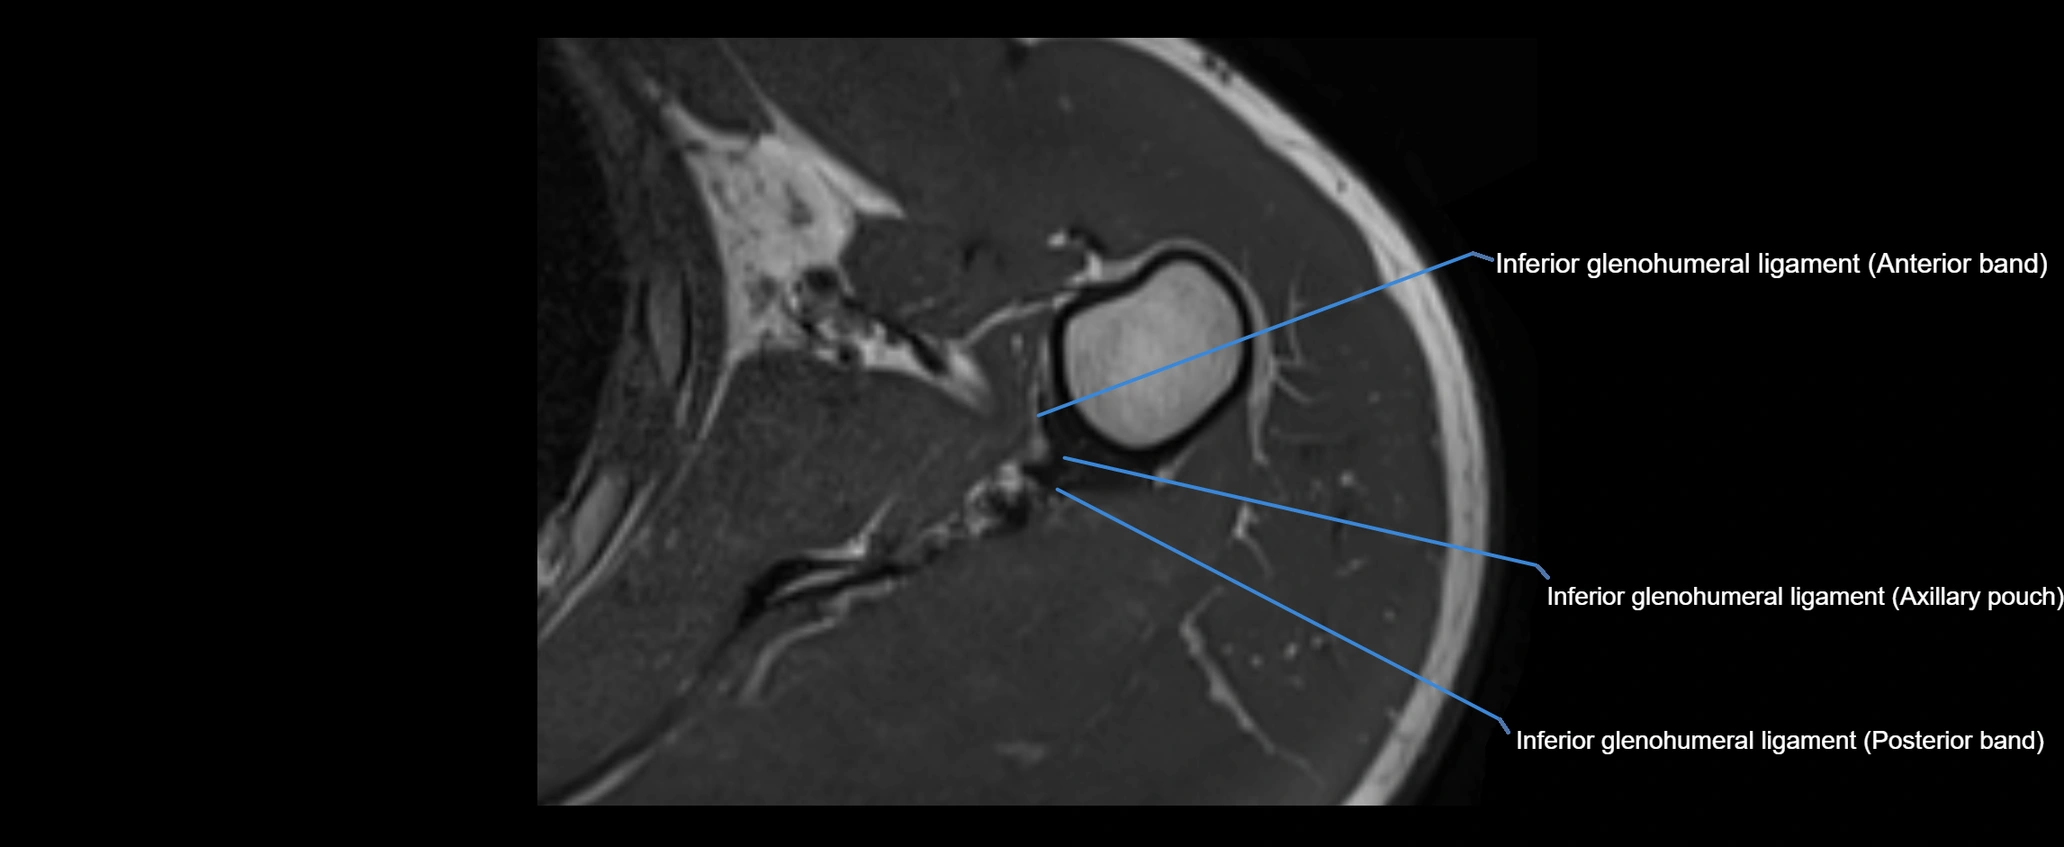

MRI images

image